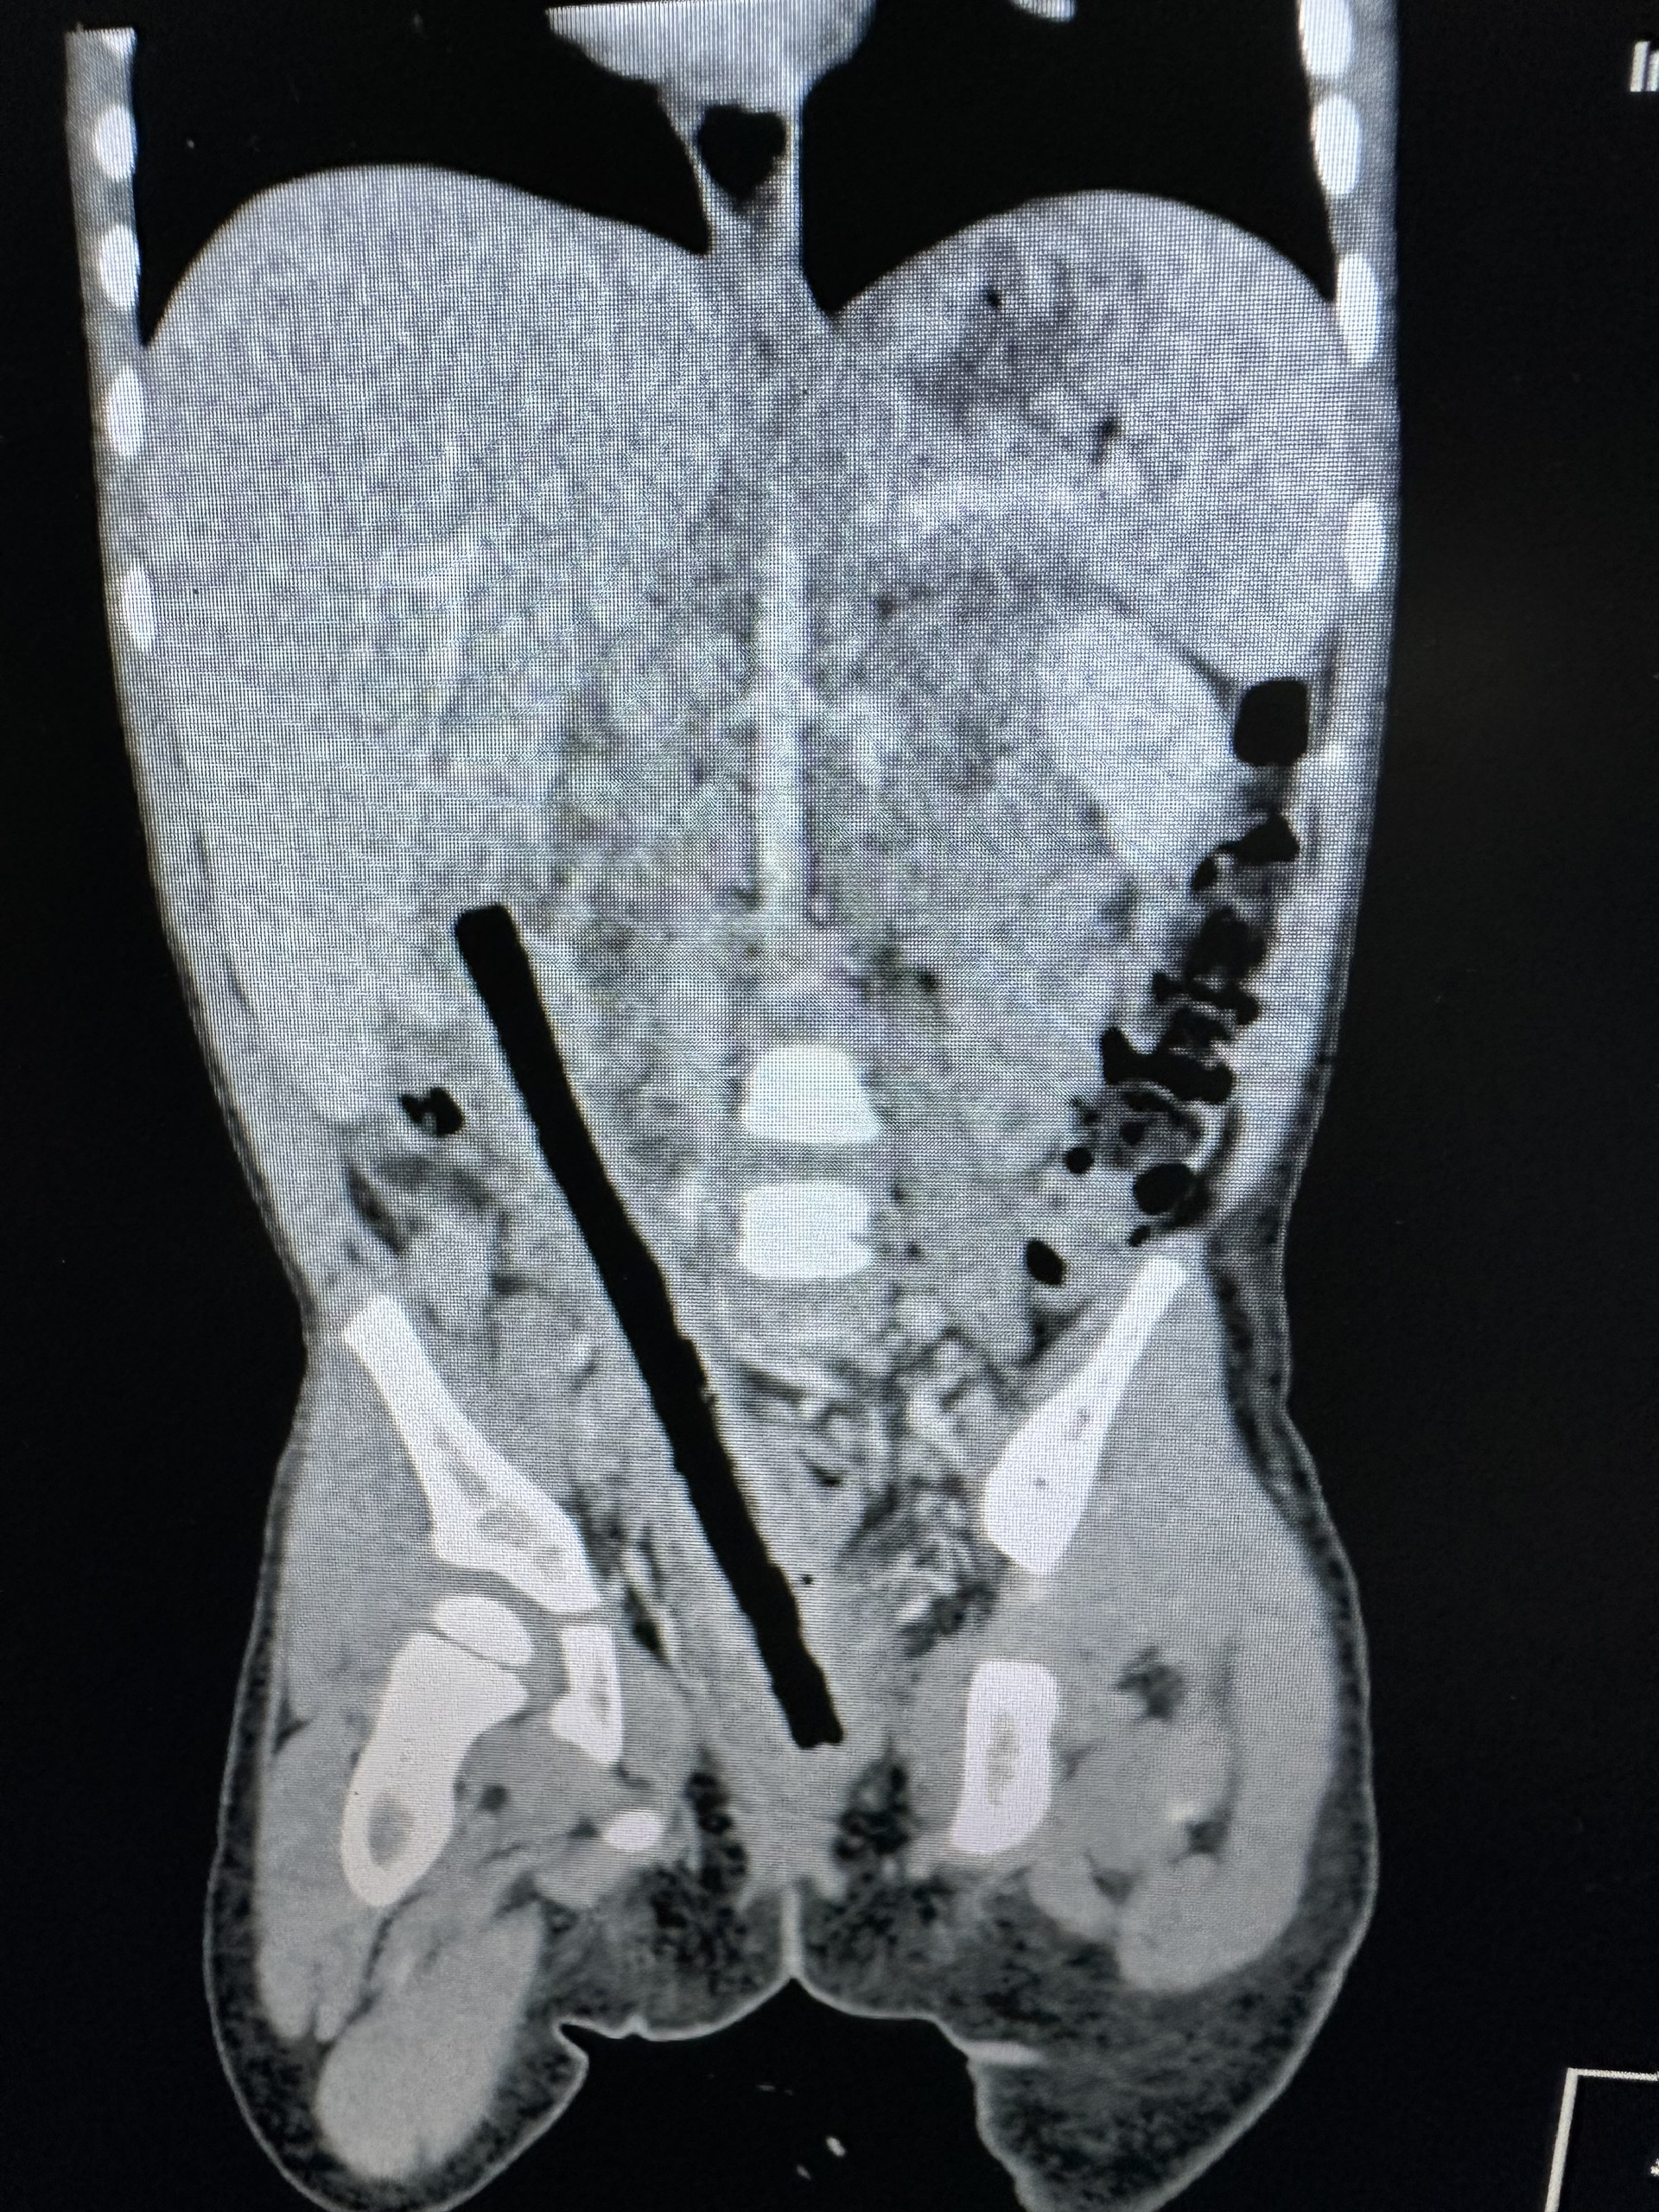

Theo BSCK1 Nguyễn Hiền, Khoa Ngoại tổng hợp – Bệnh viện Nhi Đồng 2, kết quả CT scan cho thấy trong ổ bụng bệnh nhi có dị vật kích thước 1×16 cm nằm vùng từ trực tràng đến gan.

Ê-kíp nội soi xác định dị vật đâm xuyên trực tràng, ruột non và tá tràng viêm dính nhiều, gây khó khăn cho phẫu thuật. Các bác sĩ tiến hành mổ mở bóc tách dọc theo dị vật, tách dính toàn bộ ruột, tránh làm tổn thương các mạch máu thần kinh và niệu quản, hạn chế các tổn thương các bộ phận khác.

Sau 4 giờ phẫu thuật, các bác sĩ đã lấy ra nguyên vẹn nhành cây dài 16 cm. Bệnh nhi được xử lý cầm máu, khâu các vết thương và làm hậu môn tạm. Hiện bé đang dần hồi phục và dự kiến sẽ xuất viện sau 1 tuần.